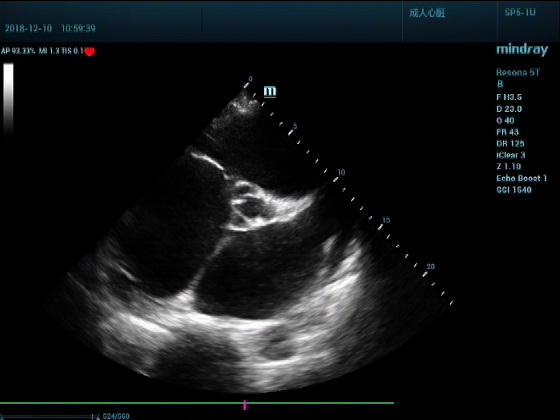

病例二:

男,81岁,全身浮肿来住院

超声可见:左房,右房,右室明显增大,主肺动脉及右肺动脉增宽,二尖瓣中度反流,三尖瓣重度反流,肺动脉轻度高压,心律不齐

心包积液盆腔积液。淤血性肝增大,肝静脉增宽。(右心衰声像改变)